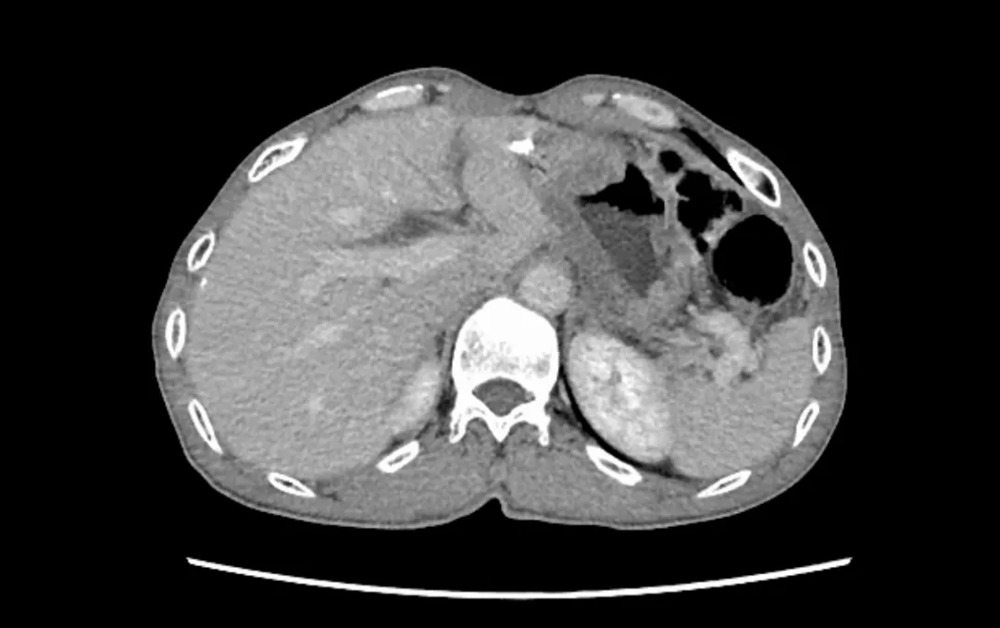

二、胸外科:高难微创,勇克双侧多原发肺癌

胸外科在复杂肺癌手术领域不断突破。一例55岁女性患者,CT发现双肺多发结节,高度怀疑多原发肺癌。面对传统分期手术创伤大、恢复慢的挑战,经多学科(MDT)充分评估、精密协作,胸外科团队勇于创新,成功为患者实施了“单孔胸腔镜下同期双侧肺癌根治术(右肺上叶切除+左肺下叶背段切除+双侧纵隔淋巴结清扫)”。手术一次完成,极大减少了患者痛苦与住院时间。术后病理证实为双侧原发性肺癌,分期分别为IIB期和IA2期。患者术后恢复迅速,第二天即可下床活动,并接受规范的靶向治疗(口服奥希替尼)。至今随访2年,无复发迹象,生活质量高。此案例彰显了我院胸外科在高难度、微创化、个体化肺癌手术治疗方面的卓越实力。